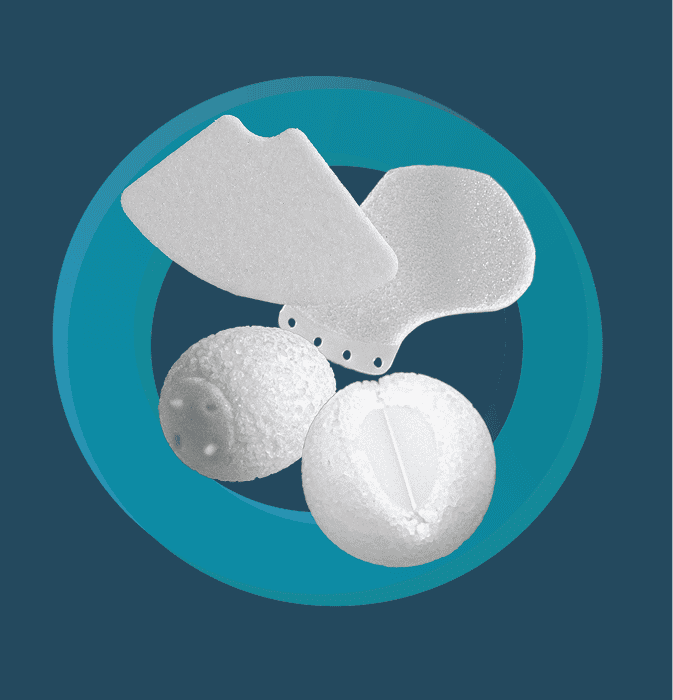

Explore Orbital Implants

Sphere

Cor-Tec Sphere

Quadro-Port Tunnel Orbital Sphere

Quadro-Port Tunnel Conical Orbital

Conical Orbial Implant

3D Orbital Floor

Floor-Tec Composite Orbital Floor

Channel Sheet

Signle Channel Sheet

Fan Plate

Orbital Floor Plate

Lower Eyelid Implant

AIRO Implnat